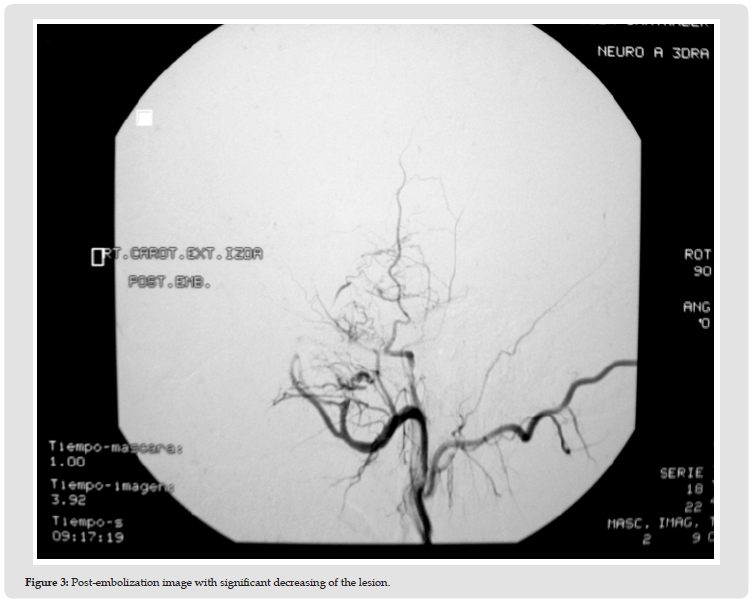

Due to aesthetic concerns and continuous growth, surgical excision was recommended. Before the surgery, a subselective arteriography was performed. In the pre-embolization images, a hypervascularized mass depending on branches of the left internal maxillary artery was identified (Figure 2). The tumor was embolized using polyvinyl alcohol microparticles, and liquid coils in the left internal maxillary artery’s pedicle, showing significant decrease of the lesion in the post-embolization images (Figure 3). One day following embolization, the patient underwent surgical removal of the hemangioma using a hemicoronal approach with preauricular and submandibular incisions. External carotid artery was temporally clamped due to the possible intraoperative bleeding. The left temporalis muscle within the angiomatous mass was then totally excised to the coronoid process, after removal of the zygomatic arch and ligation of the left maxillary artery at the liquid coil’s level. The zygomatic arch was then replaced, and the defect filled with a temporal polyethylene implant. On the histological examination, the tumor was composed of a large number of interconnecting endothelial-lined vascular spaces in skeletal muscle, consistent with an intramuscular haemangioma of the capillary type. The patient had an uncomplicated postoperative recovery, achieving favorable functional and cosmetic outcomes. Nine years after the surgery, there are no signs of recurrence